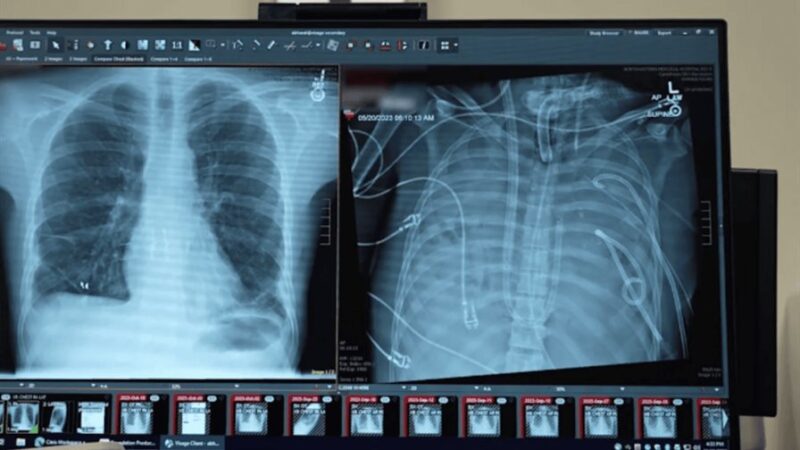

La enfermedad se desencadenó tras una gripe, que posteriormente se complicó con una neumonía bacteriana, provocando daños irreversibles en los pulmones, con el avance del cuadro clínico, el deterioro se extendió también al corazón y los riñones comprometiendo gravemente su vida.

Una vez retirados los pulmones infectados la condición del paciente comenzó a mejorar notablemente, su presión arterial se estabilizó, la función de sus órganos se recuperó progresivamente y la infección cedió, dos días después llegaron pulmones compatibles de un donante y los cirujanos procedieron a realizar con éxito el trasplante doble de pulmón.

El análisis de los pulmones extraídos reveló cicatrización generalizada y daño inmunológico severo, señales claras de que el tejido no podía recuperarse por sí mismo, por primera vez el equipo aportó pruebas moleculares que confirman que ciertos pacientes con SDRA no sobrevivirán sin un trasplante doble de pulmón.